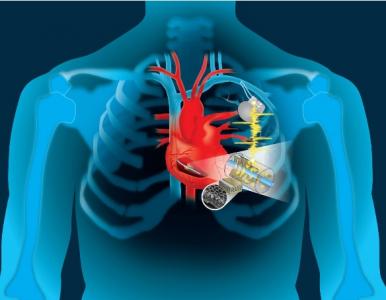

Exploiter la puissance du rythme cardiaque pour recharger son stimulateur ou « les batteries du coeur », c’est la grande idée de cette équipe du Collège de Dartmouth (US) : elle a mis au point un dispositif de moins de 2 cm de diamètre qui capte et convertit l'énergie cinétique du cœur en électricité pour alimenter une large gamme de dispositifs implantables. Ce développement astucieux présenté dans la revue Advanced Materials Technologies va trouver sa première application logique dans une nouvelle génération de stimulateurs cardiaques.

Une large application à terme, alors que la vie de millions de personnes dépend de stimulateurs cardiaques, défibrillateurs et autres dispositifs implantables, aujourd’hui alimentés par des piles, qui doivent être remplacées tous les 5 à 10 ans. Des remplacements qui nécessitent une intervention chirurgicale pénible, coûteuse et à risques de complications et d’infections.

Il fallait y penser, mais le mouvement du cœur est si puissant qu'il peut fournir l’énergie nécessaire pour recharger des dispositifs qui sauvent la vie, en maintenant le rythme cardiaque justement. Cette étude financée par les National Institutes of Health (NIH) montre comment l’énergie cinétique du cœur peut être convertie en électricité pour alimenter un dispositif implantable, grâce cette invention d’ingénieurs de la Thayer School of Engineering de Dartmouth. Ce concept apporte ainsi une solution au problème ultime de tout dispositif biomédical implantable. John X.J. Zhang, professeur d'ingénierie à Dartmouth avait ainsi recherché avec son équipe le moyen de créer ou d’obtenir une source d’énergie efficace pour que le dispositif remplisse sa fonction pendant toute la vie du patient, sans besoin d’intervention chirurgicale pour remplacer la pile. Mais il fallait aussi que l’appareil n'interfère pas avec les fonctions du corps, soit biocompatible, léger, flexible et discret, qu'il s'adapte non seulement à la structure des stimulateurs actuels, et, en même temps qu’il puisse évoluer pour accueillir une multifonctionnalité d’avenir…

Il exploite l’énergie cardiaque et en plus capte des données : Le travail de l'équipe propose de modifier les stimulateurs cardiaques pour exploiter l'énergie cinétique du fil conducteur relié au cœur, en ajoutant un matériau, un type de film polymère piézoélectrique mince appelé « PVDF » qui, lorsqu'il est conçu avec des structures poreuses peut convertir même un petit mouvement mécanique en électricité. Ce module offre un avantage supplémentaire, il peut également être utilisé comme capteur pour permettre la collecte de données pour une surveillance en temps réel des patients.

Ce stimulateur automatique pourrait être disponible d’ici quelques années : les ingénieurs estiment que d’ici environ 5 ans, le processus préclinique pourrait être achevé et il serait possible alors d’obtenir l'approbation réglementaire.